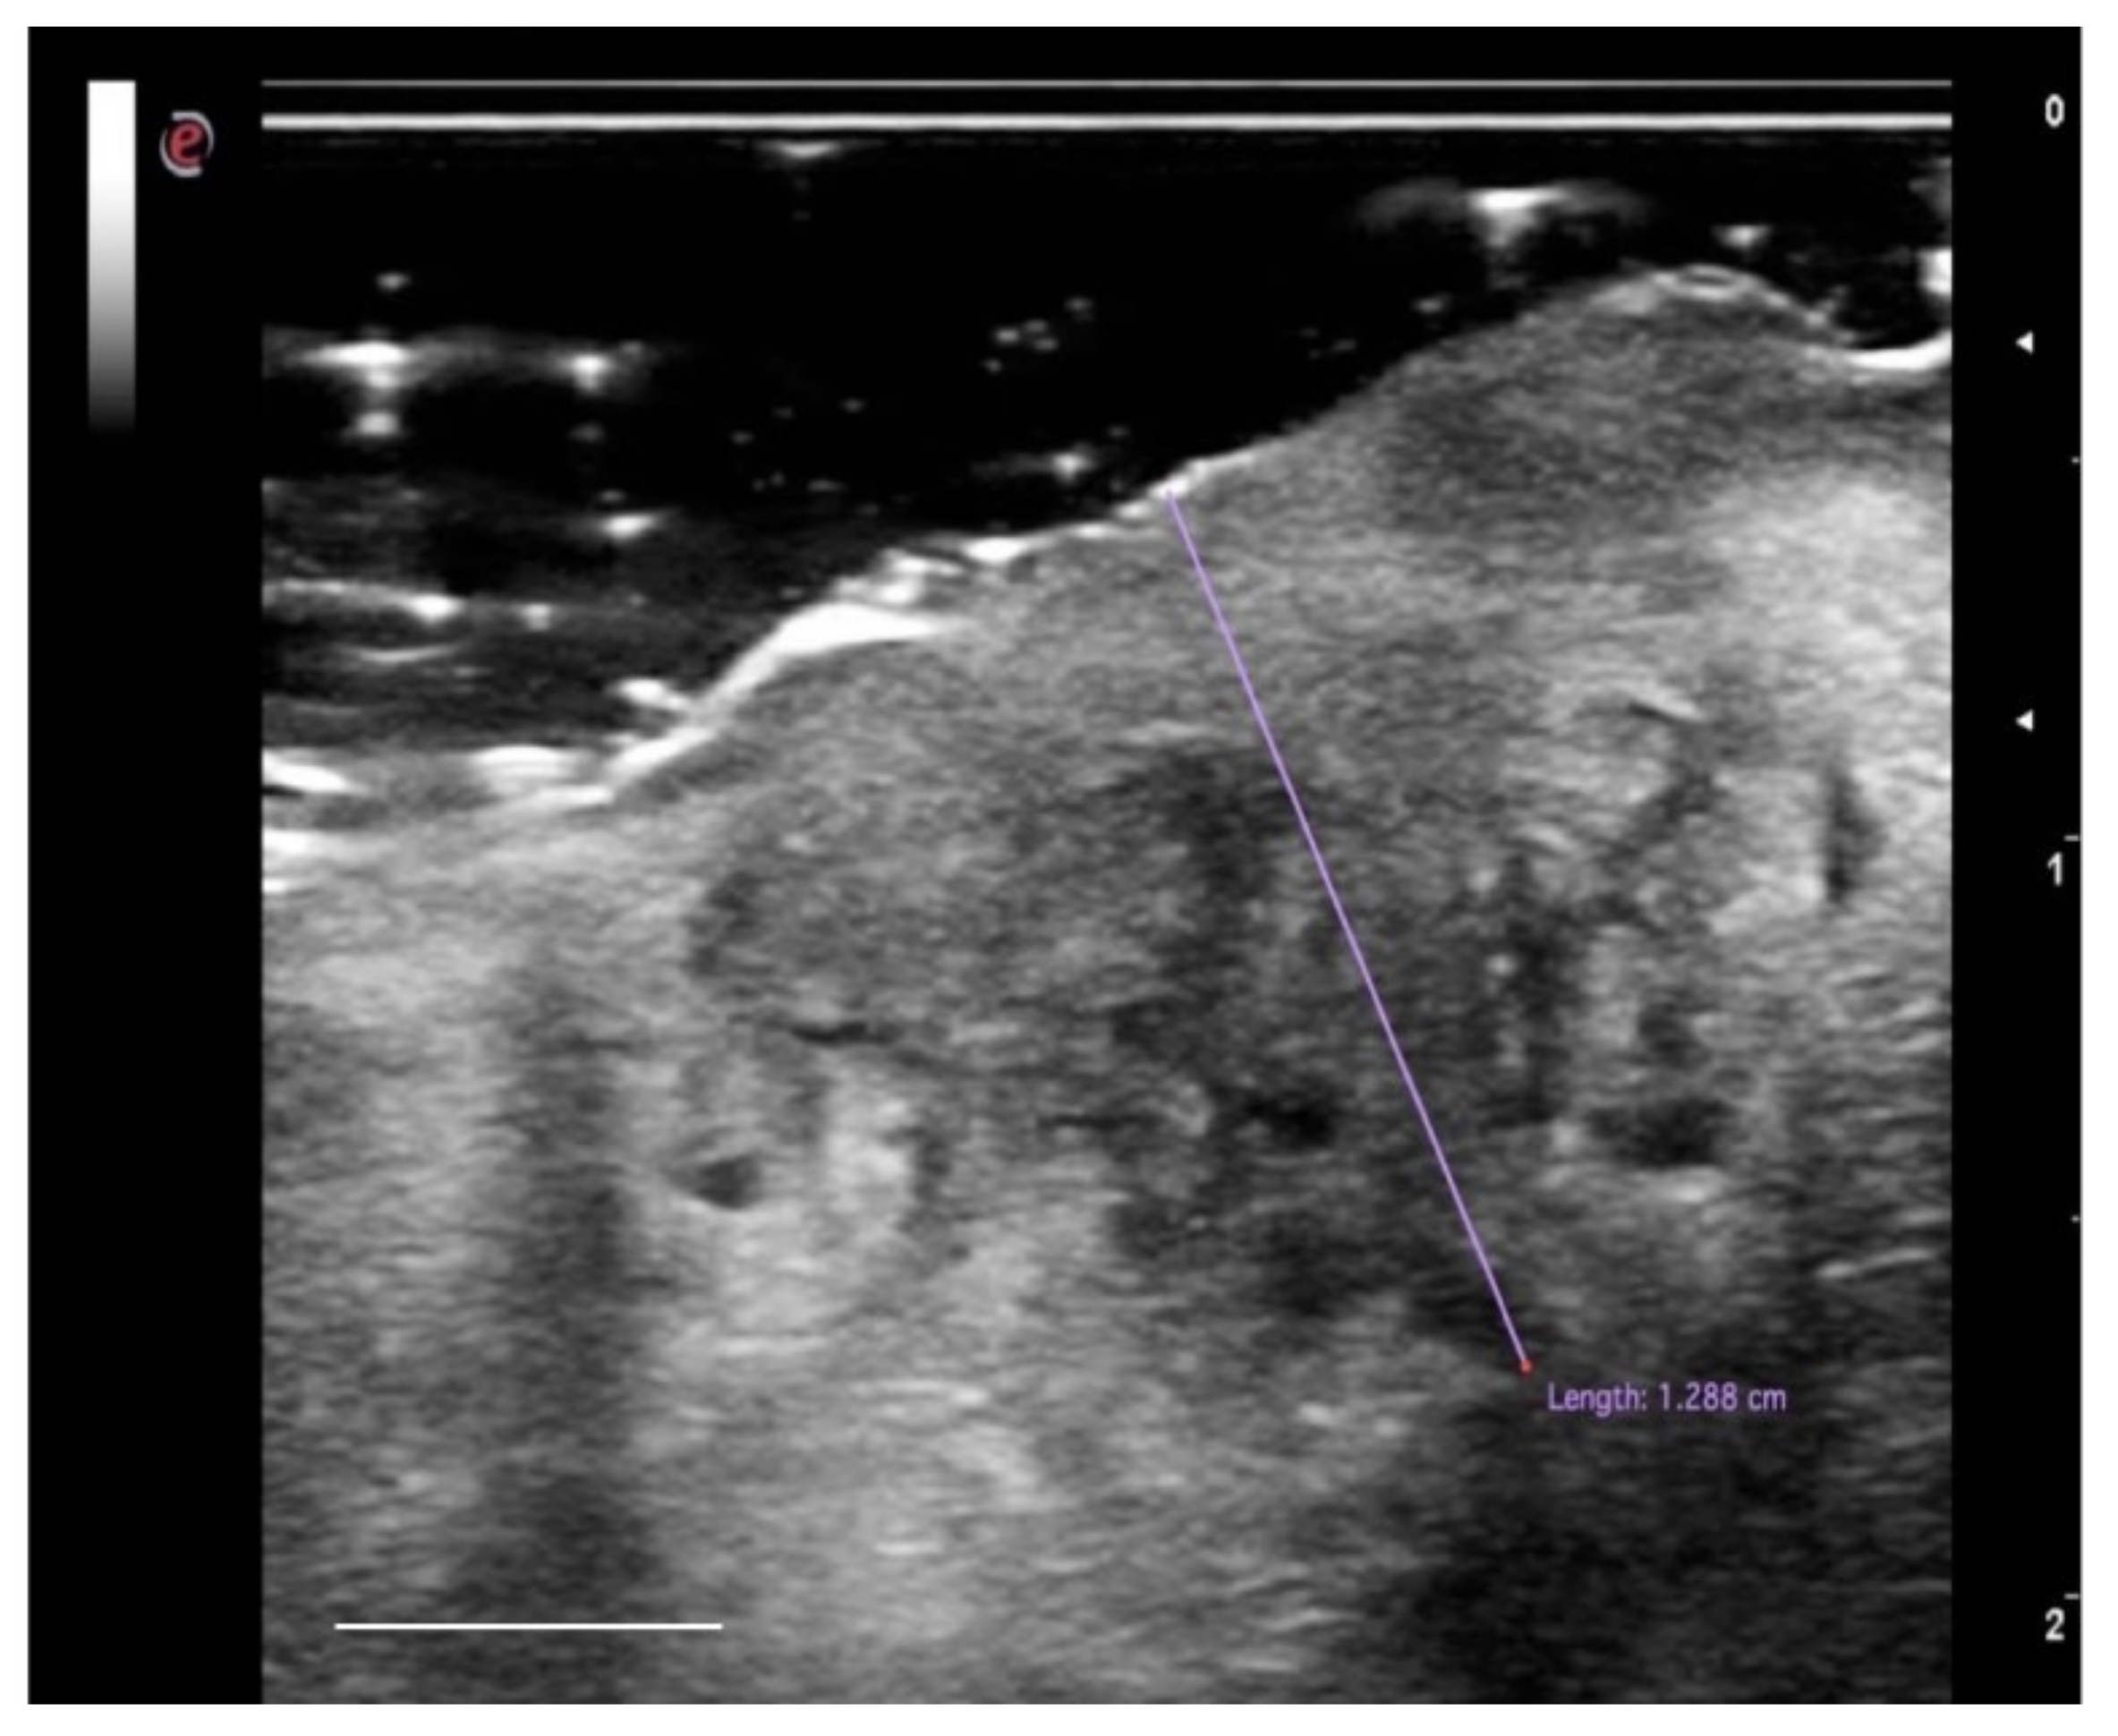

Figure 5.

High-definition US imaging (frequency 18 MHz) of a suspicious lesion of the tongue margin. The high-definition ultrasound image shows a hypoechoic area with a thickness of 1.288 cm (TT), highlighted with the purple line, in the context of the lingual parenchyma (which does not show alterations in echogenicity). The histopathological analysis revealed the presence of OSCC of the lingual margin. Scale bar, 0.5 cm.